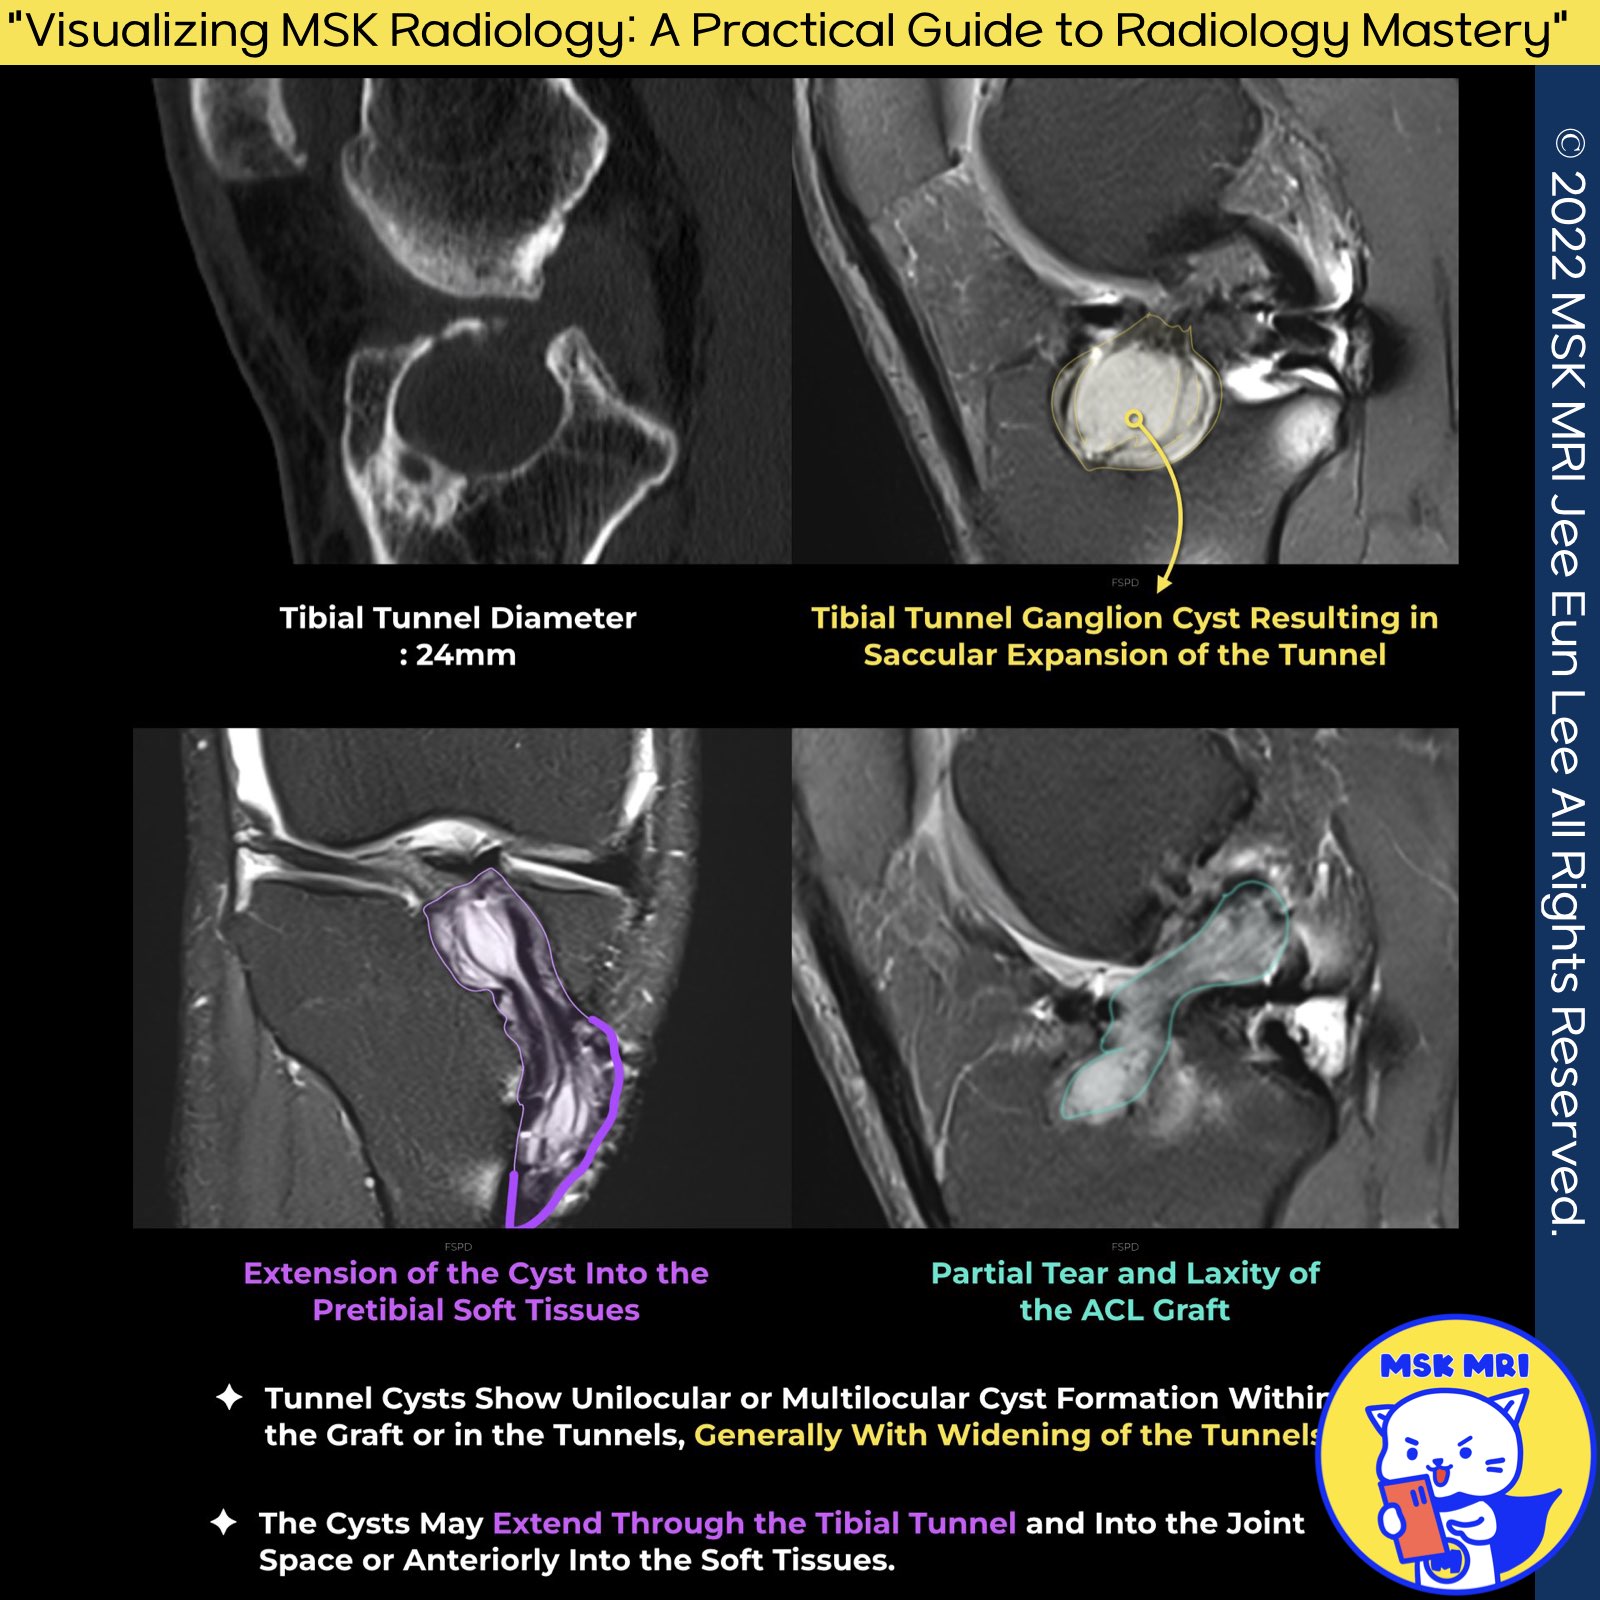

1️⃣ Definition and Indicators of Tunnel Widening

- Tunnel widening is identified as a postoperative enlargement greater than 2 mm on anteroposterior or lateral radiographs, a change that raises suspicion when observed in the parallel walls of a cone-shaped tunnel.

- This phenomenon is primarily cavitary and often peaks in the mid-zone of the tibial tunnel, occurring in the joint's plane of movement.

3️⃣ Postoperative ACL Tunnel Diameter and Graft Selection

- Immediately after ACL reconstruction surgery, the expected tunnel diameter should be around 10 mm, regardless of the graft selection.